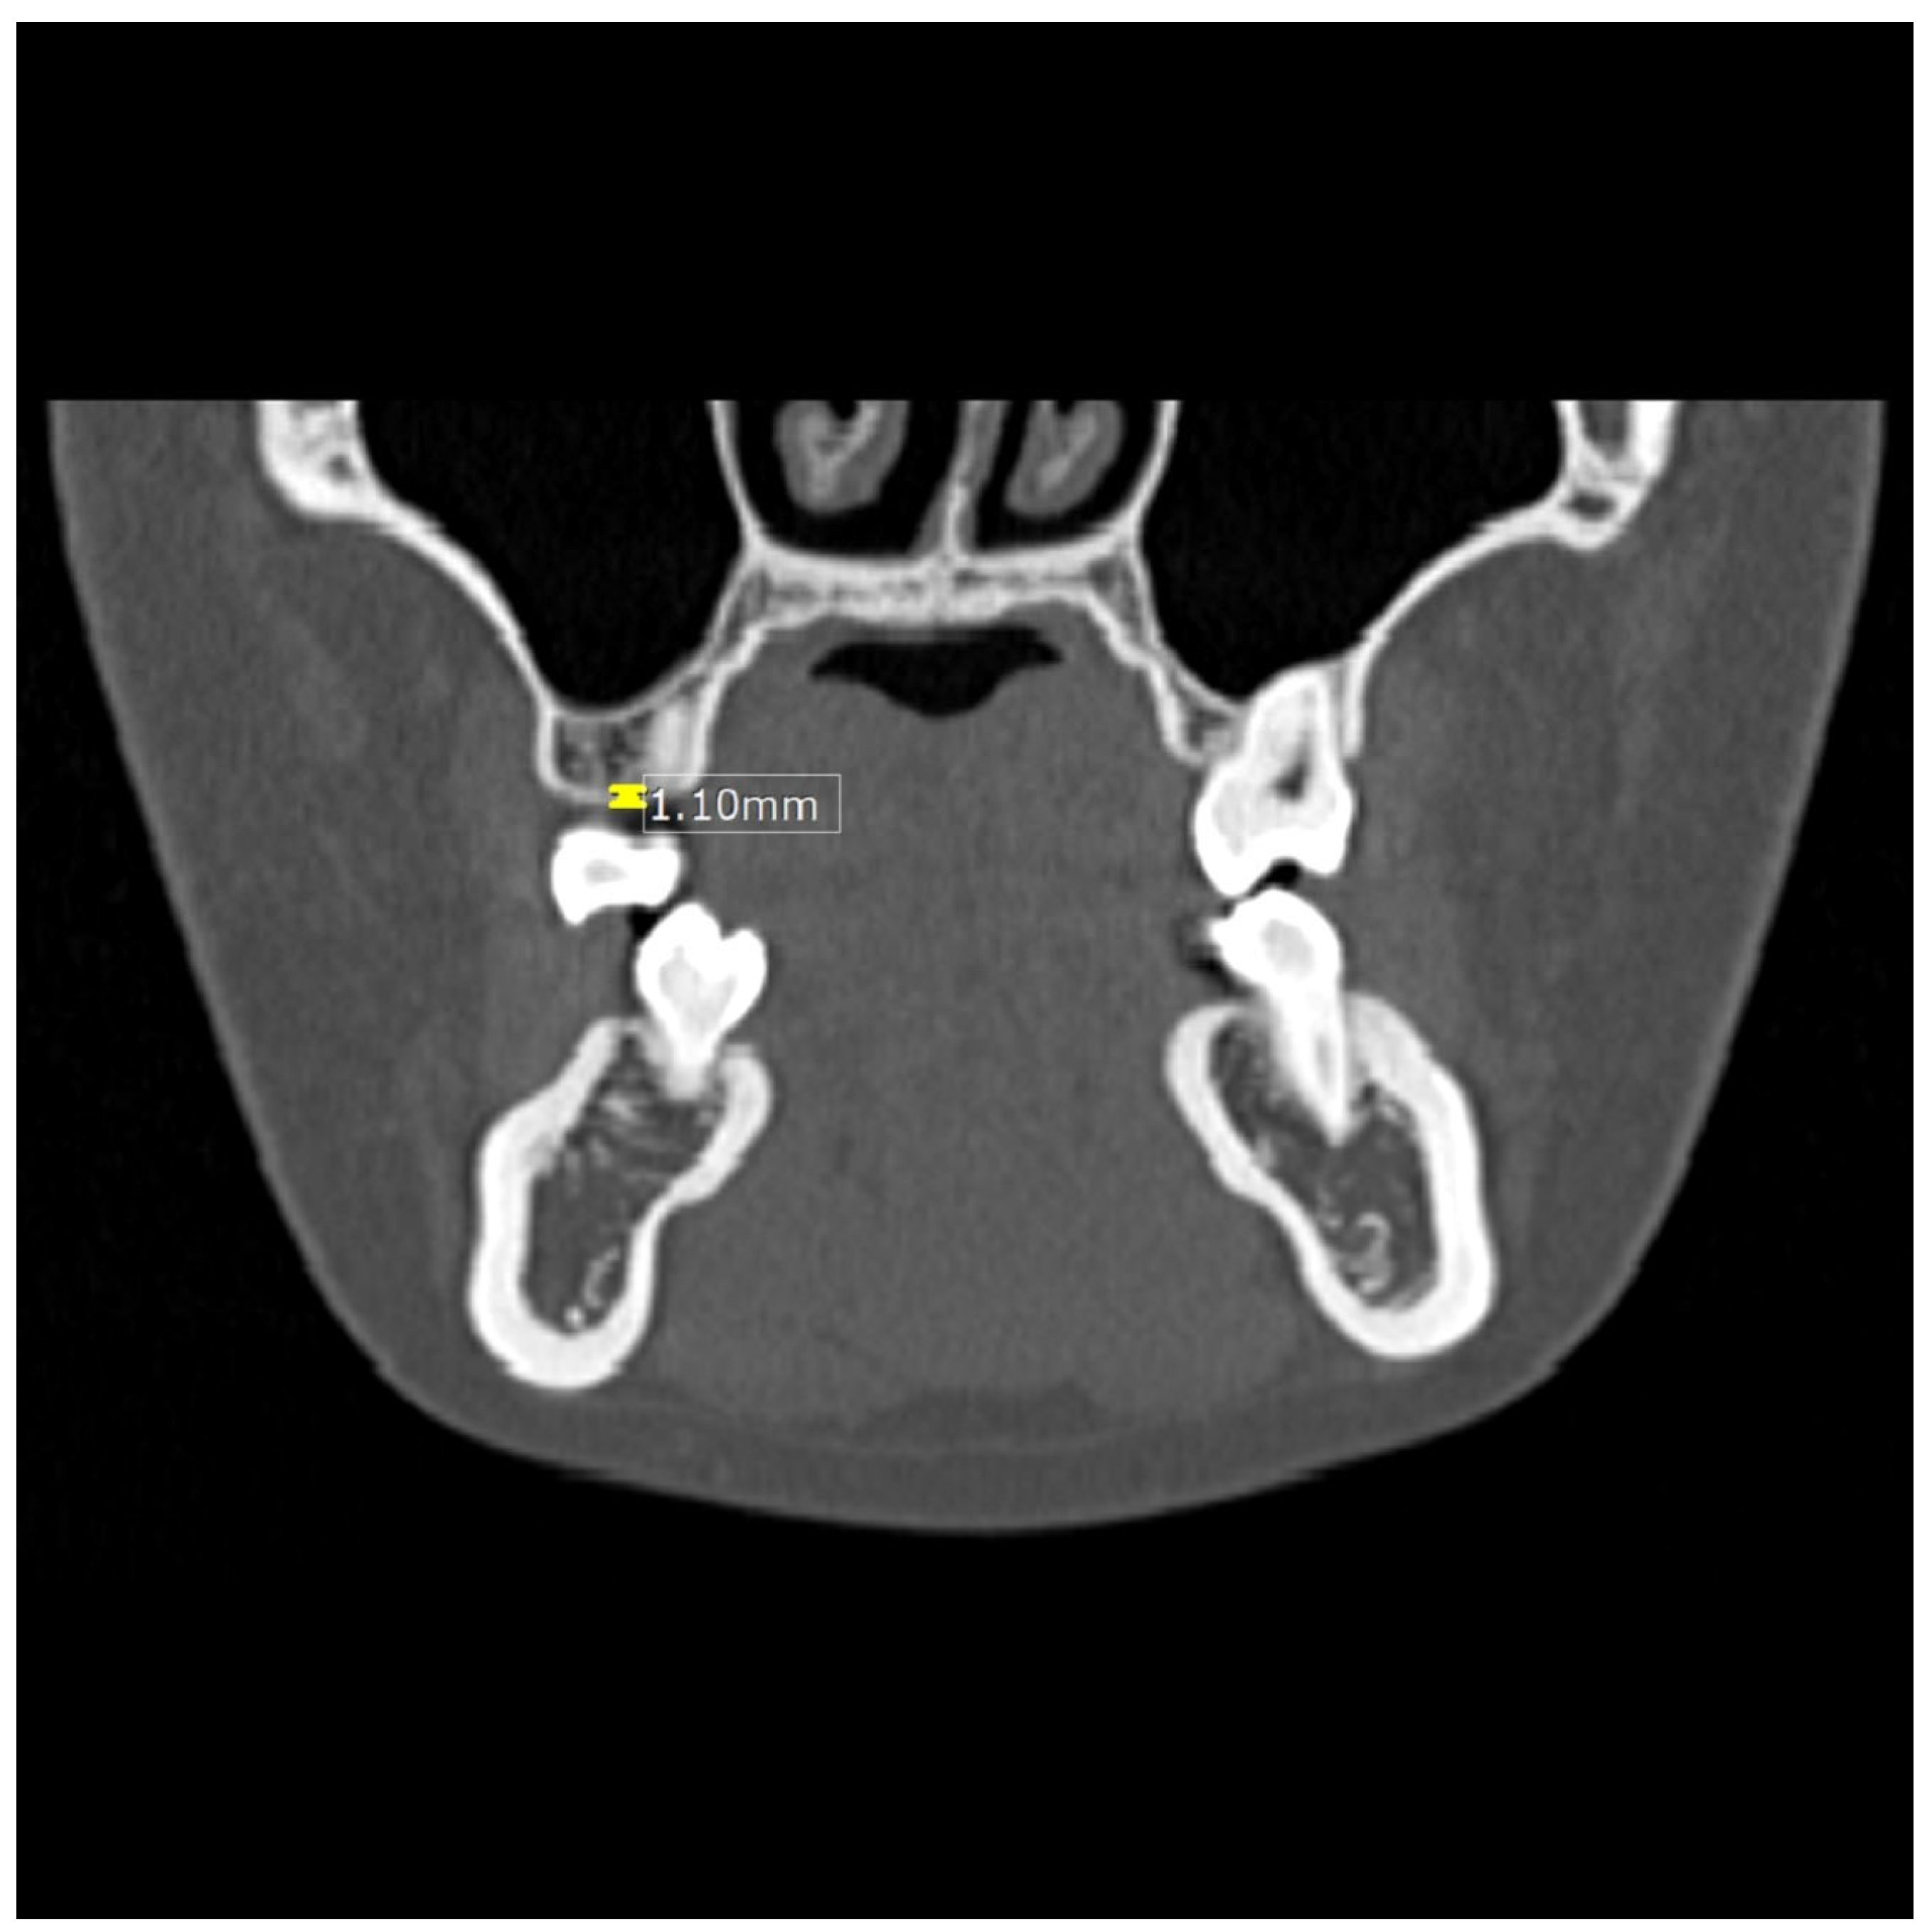

2.3. CT Imaging Analysis

| Tmax3 | thickness between the maxillary canine and first premolar |

| Tman3 | thickness between the mandibular canine and first premolar |

| Tmax6 | thickness between the maxillary premolar and first molar |

| Tman6 | thickness between the mandibular premolar and first molar |